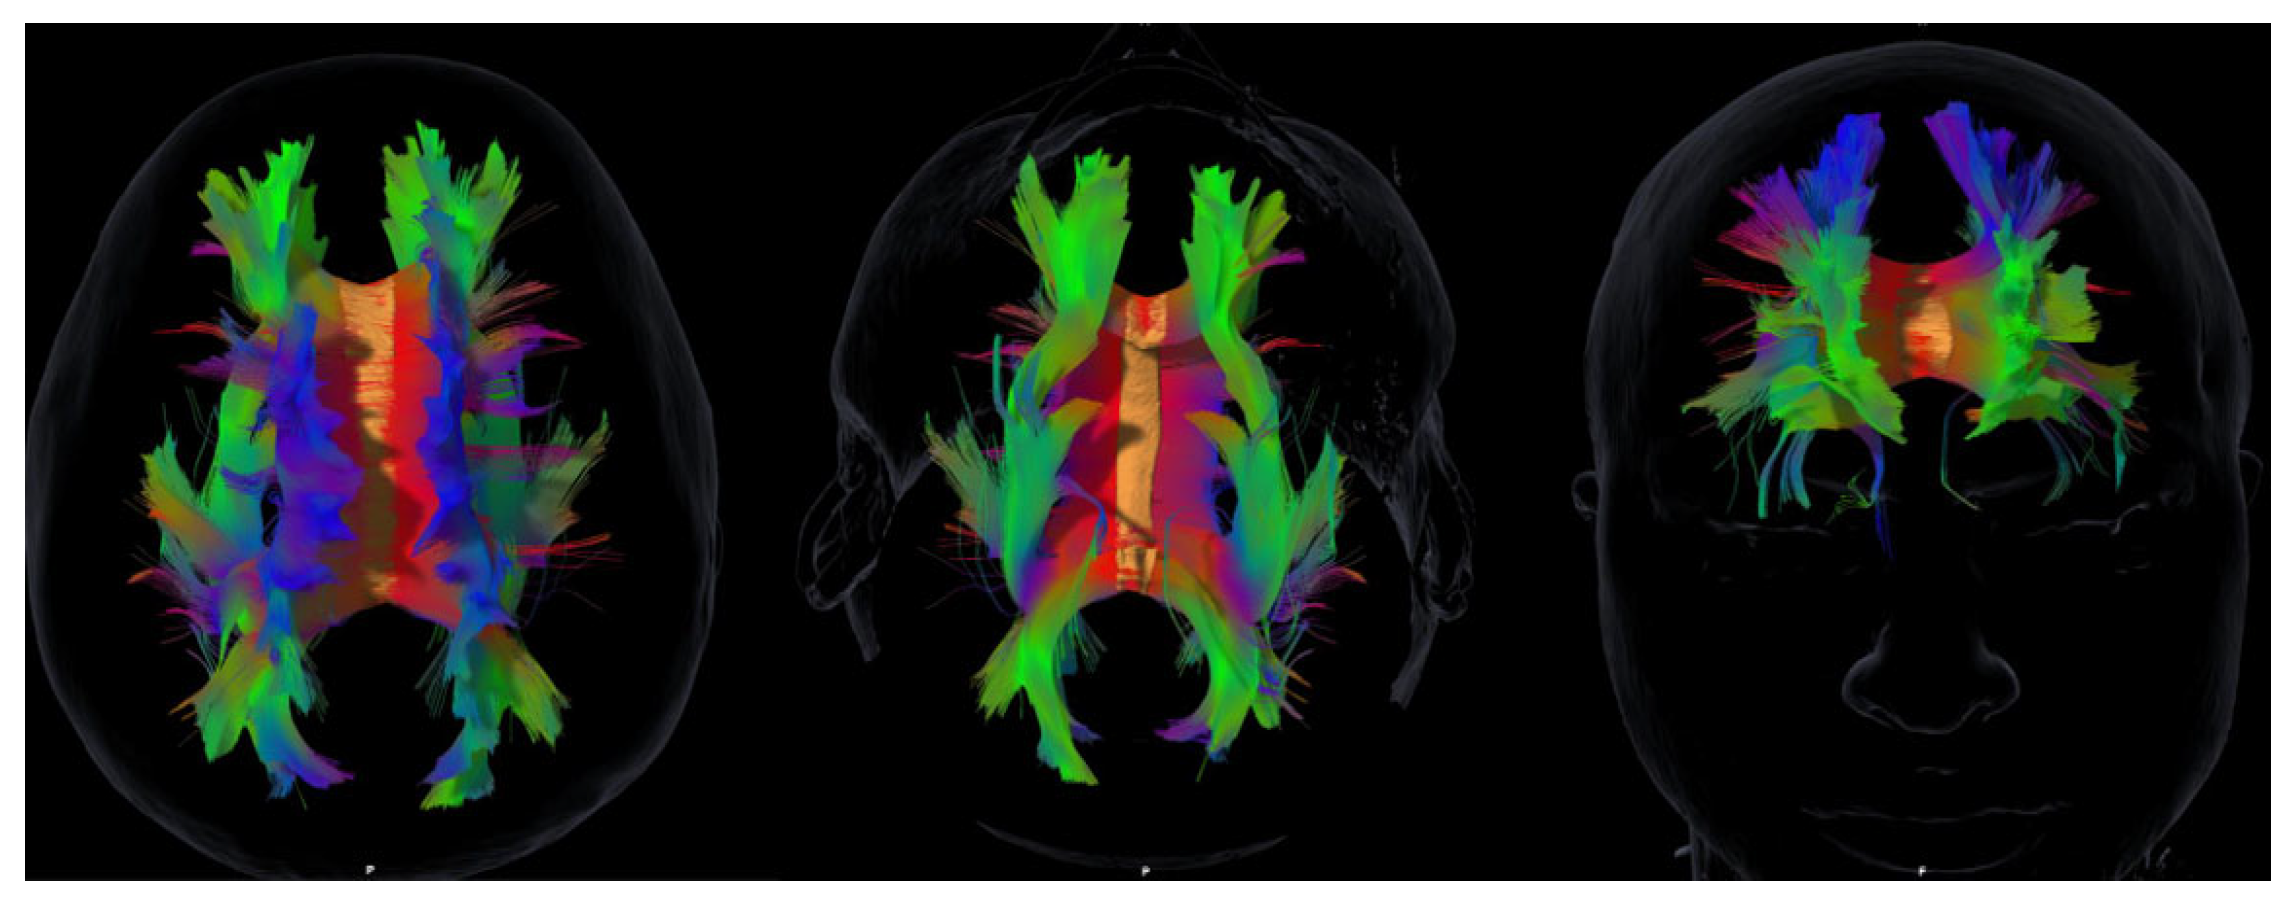

Background: Acquired brain injury (ABI) leads to cognitive, emotional, and social impairments that substantially affect quality of life. Although cortical lesions have traditionally received more attention, increasing evidence highlights the importance of the integrity of major white matter association tracts. However, few studies have simultaneously examined cognitive, affective, and social domains within a tractography framework.Methods: In this exploratory pilot study, ten ABI patients underwent diffusion-based tractography of the principal association tracts—the superior and inferior longitudinal fasciculi, the uncinate fasciculus, the inferior fronto-occipital fasciculus, and the cingulum—together with a comprehensive neuropsychological battery covering global cognition, executive functions, memory, emotional symptoms, and empathy. Results: Marked interindividual variability was observed in both tract profiles and neuropsychological outcomes. Findings revealed paradoxical associations, such as larger volumes of the left superior longitudinal fasciculus being linked to poorer cognitive performance, suggesting maladaptive reorganization. Hemispheric lateralization patterns were also identified, with the uncinate fasciculus showing differential contributions to immediate memory and working memory across hemispheres. Notably, empathy scores consistently correlated with volumes of the inferior longitudinal fasciculus, the uncinate fasciculus, and the cingulum, in line with recent evidence on the structural basis of socio-emotional outcomes after ABI. Conclusions: Although limited by sample size, this study provides novel evidence regarding the structure–function paradox, hemispheric specialization, and the clinical relevance of empathy in ABI. Overall, the results support the integration of tractography of the main association tracts with neuropsychological assessment as complementary tools to advance personalized neurorehabilitation.

2.3. MRI Acquisition and Tractography

3.3. White Matter Tract Volumes